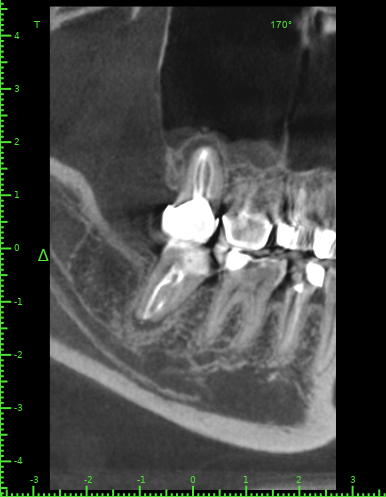

Katya88 Опубликовано 28 июля, 2021 Поделиться Опубликовано 28 июля, 2021 Мой стоматолог терапевт советует удалить, так как там кисты, а ортопед советует найти того, кто займется лечением. КТ прилагаю https://drive.google.com/file/d/1Z-neEH63BszTXxa8bAOG1tgsrIrsqrVK/view?usp=drive_web Ссылка на комментарий

Женька Опубликовано 28 июля, 2021 Поделиться Опубликовано 28 июля, 2021 2.6 2.7 3.7 На 3.5 и 1.5 стоит обратить внимание 1.5 1 Ссылка на комментарий

Женька Опубликовано 28 июля, 2021 Поделиться Опубликовано 28 июля, 2021 54 минуты назад, Katya88 сказал: 1.5 менять коронку как минимум снять существующую конструкцию и посмотреть клинически на зуб(ы). 1.5 на КТ выглядит удручающе. По остальным, я бы поддержал ортопеда и попытался зубы сохранить. Пусть коллеги меня поправят. 1 1 Ссылка на комментарий